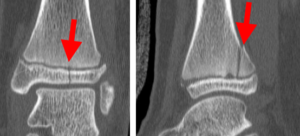

In children and adolescents, ankle fractures typically affect the tibia or fibula, often involving the growth plates—specialized areas of cartilage near the ends of long bones. Growth plates play a critical role in bone development, gradually hardening into solid bone as the child matures. However, because these growth plates are the last parts of the bones to solidify, they are particularly prone to injury and fractures. As adolescents approach the end of their growth phase, growth plates begin to close and harden, making them susceptible to transitional fractures during this maturing stage. Two common types of transitional ankle fractures are triplane fractures and Tillaux fractures, which require specific treatment approaches depending on their severity and location (refer to the Treatment section for more details)